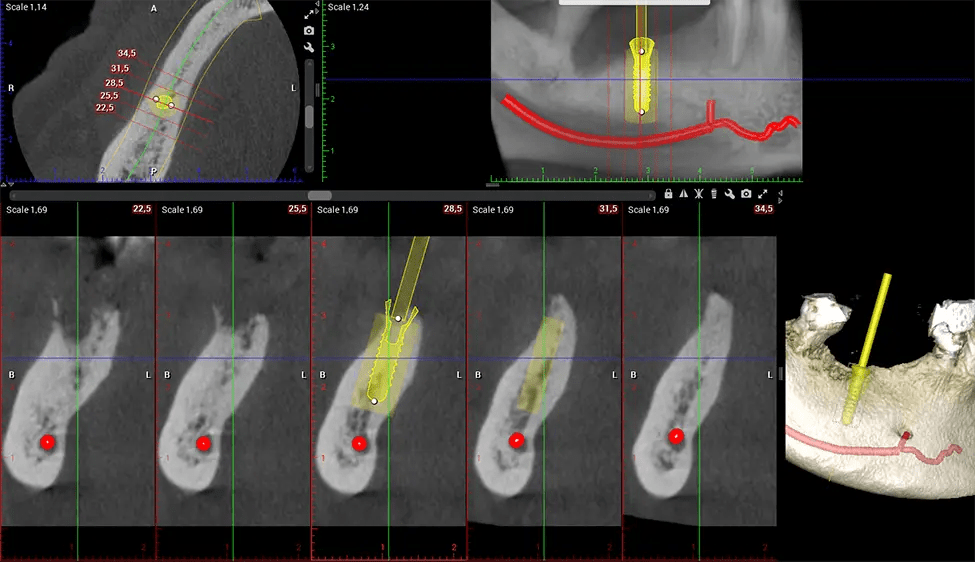

When paired with extractions, dental implant placement, or bone grafting, CBCT technology can provide you with a quicker and much more comfortable experience. This is because the 3D image provides a more detailed picture of your entire oral cavity, allowing your dentist to walk you through each step of the process before it occurs. This often helps patients feel more prepared and comfortable overall, especially if they have had a traumatic experience with past dental treatments.

After the scanning process, the captured X-ray images are processed by the CBCT software, which applies algorithms to reconstruct a detailed 3D image of the scanned area. The software compiles these individual X-ray images and creates a digital 3D representation of the patient’s anatomy. The reconstructed 3D CBCT image can be viewed and analyzed by the dentist or radiologist. This image can be manipulated, rotated, and zoomed in or out to examine specific structures and evaluate the patient’s condition.

Planmeca Viso G7 CBCT ( Cone Beam CT Scan ) is designed to surpass the demands of industry leaders, specialists, and large institutions. It’s has a large ø25×30 cm sensor with four built-in cameras. It can capture unlimited volume sizes from a ø3×3 cm to a ø30x30cm volume capturing the skullcap through C7 on the cervical spine. The Planmeca Viso G7 offers the industry’s largest single volume scan of ø30×19 cm. It’s poised to handle advanced imaging modalities such as Planmeca ProFace® and Planmeca 4D™ Jaw Motion technology. The occipital head support allows an unimpeded view of facial tissue.

Planmeca is the only manufacturer clinically proven to dramatically reduce patient radiation without sacrificing image quality. Planmeca Ultra Low Dose™ achieves an average reduction in dose of 77% without a statistical reduction in image quality allowing doctors to incorporate 3D imaging into routine protocols with effective patient radiation often lower than 2D intraoral imaging. This increases patient care, allows doctors to diagnose more dentistry, and often earlier in disease progression, than with 2D imaging alone.

Our patented SCARA technology enables doctors to capture True Extraoral Bitewings that are as accurate at detecting caries as a 2D bitewing series, but with half the radiation dose. With our bitewings, doctors can view the apices of teeth on both jaws providing a more comprehensive view of the patients’ anatomy.